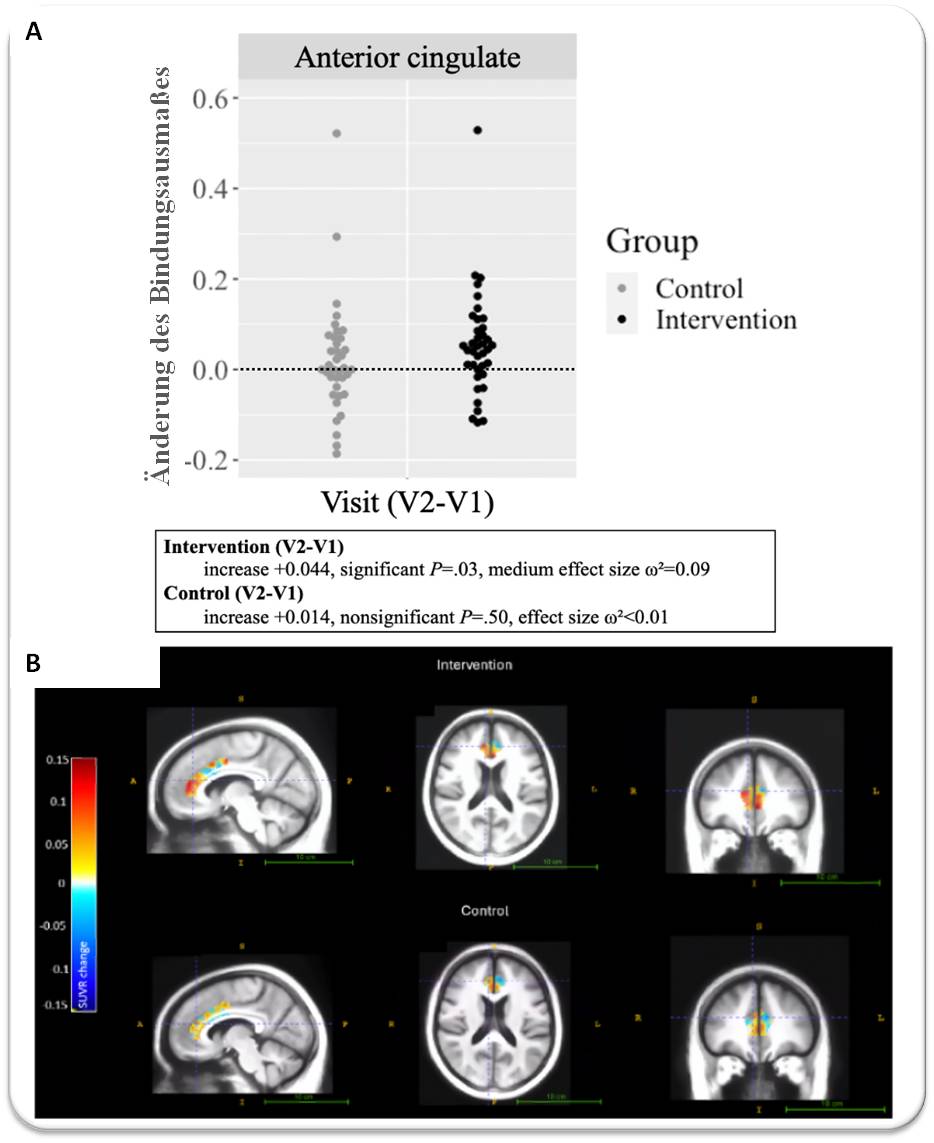

Die Auswirkungen der Trainingsprogramme

wurden dann mittels PET auf die Bindung des [18F]-Radioliganden im anterioren cingulären Kortex untersucht und quantifiziert; diese Gehirnregion ist an einer Vielzahl von kognitiven Prozessen beteiligt, u.a. an Aufmerksamkeitsprozessen, Erkennen von Fehlern, Belohnungslernen, Entscheidungen und Verarbeitung von Schmerz. Die Messungen wurden zu Beginn der Studie, nach dem Test und anlässlich einer Nachuntersuchung 3 Monate später durchgeführt, um die Erhaltung beobachteter Effekte zu messen.

Abbildung 3. Veränderung der Bindung des [18F]-Radioliganden im anterioren cingulären Kortex. A) Nach 10 Wochen Training im Vergleich zum Ausgangswert. Jeder Punkt ist der Änderungswert eines einzelnen Teilnehmers. Höhere Werte weisen auf einen stärkeren Anstieg der Bindung hin. B) Bindungsänderung nach dem Test gemittelt über die Teilnehmer. Oben Intervention, unten Kontrolle. Wärmere Farben zeigern stärkeren Anstieg der Bindung an. (Bild Figure 3 leicht modifiziert aus Attarha M. et al.,2025. doi: 10.2196/75161 [5]. Lizenz: cc-by.) |

Das Ergebnis war verblüffend: Am Ende des Trainings zeigte die Brain HQ-Gruppe im anterioren cingulären Kortex einen signifikanten Anstieg der Acetylcholin-Produktion um 2,3 % (Abbildung 3), einem Wert, der bei normaler Alterung einem um 10 Jahre jüngeren Alter entsprechen würde (wie oben erwähnt, sinkt der Acetylcholin-Spiegel kontinuierlich um etwa 2,5 % im Jahrzehnt).

Im Gegensatz dazu blieb der Acetylcholinspiegel der Gruppe, die Double Klondyke Solitaire und Bricks Breaking Hex spielten, unverändert (Abbildung 3).